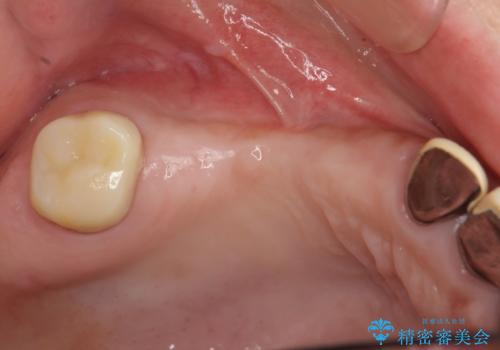

インプラントが長持ちするために、インプラント周囲の十分な骨量・角化歯肉の存在・安定した咬合を一つづつ整備する治療を行いました。